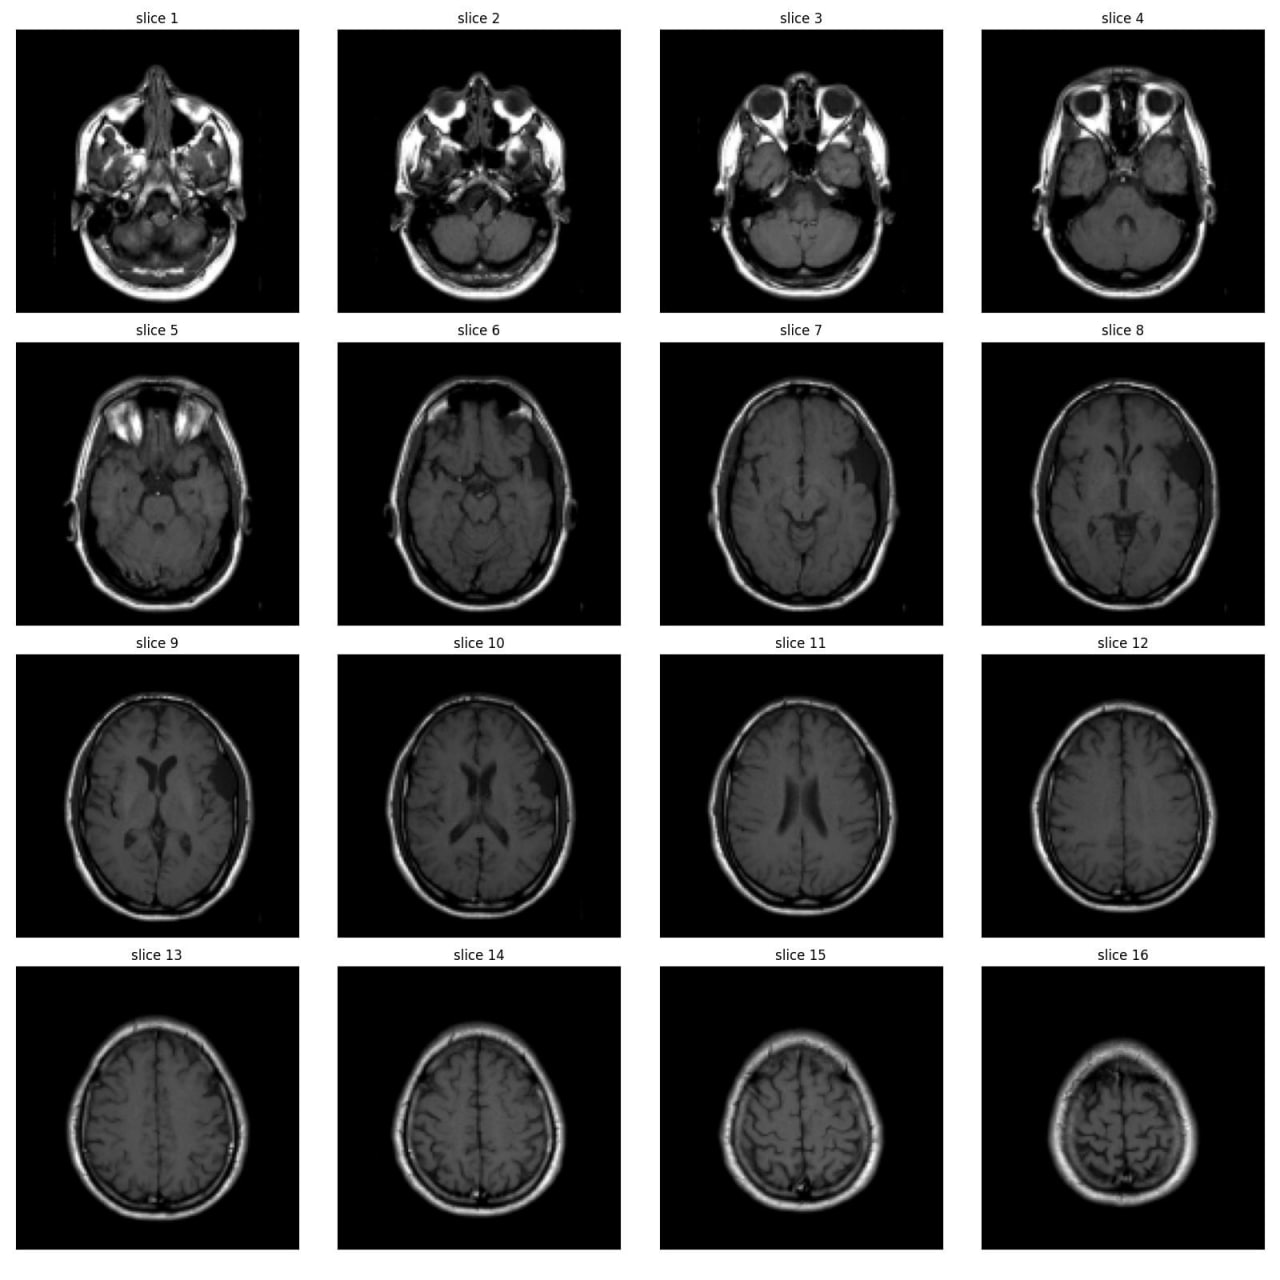

Abnormality Classification in Brain MRI

As part of the JIM3 team, I competed in the IAAA competition, which involved a dataset of 4,000 MRI images, with only 500 labeled as abnormal. The competition aimed to develop a model for patient-level abnormality classification. We utilized various models, including EfficientNet, DenseNet, ResNet, custom CNN models, and Vision Transformers (VIT), along with different preprocessing techniques. Working closely with a medical team, we converted subject-level annotations into slice-level annotations for more effective model training. Despite discovering inconsistencies in the test set and normal cases after the competition, we secured 17th place among over 100 teams. The technical team is currently working on a paper using the annotated data from this project.